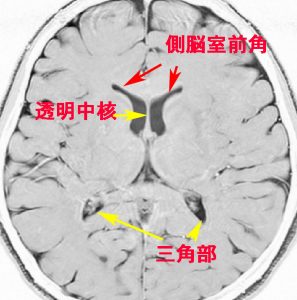

側脳室

第3脳室と第4脳室